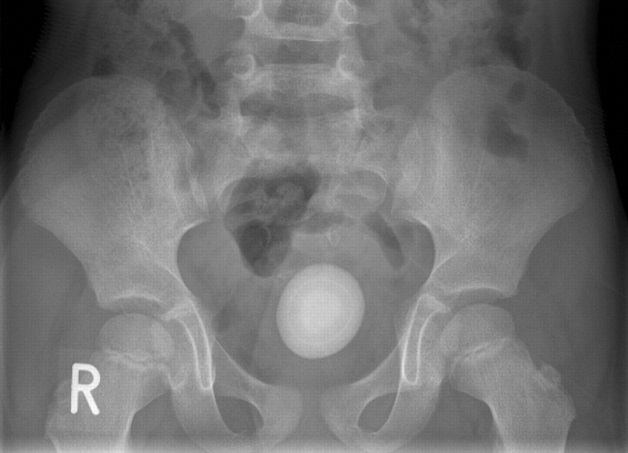

Hình ảnh một viên sỏi bàng quang với kích thước tương đối lớn.

– Chụp CT, chụp X quang, siêu âm: các phương pháp chẩn đoán hình ảnh này cho phép bác sĩ có thể quan sát chi tiết bên trong bàng quang để xác định kích thước, vị trí và hình dạng của viên sỏi.